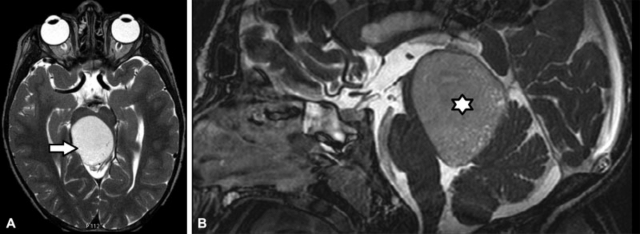

Se caracteriza por la dilatación quística de la fosa posterior con comunicación del IV ventrículo, agenesia o hipoplasia del vermis cerebeloso (con rotación cefálica del remanente vermiano) y desplazamiento cefálico del tentorio y senos laterales (►Fig. 19).5,11,16 El diagnóstico se realiza en forma prenatal mediante ecografía y RM; después del nacimiento se prefiere la RM.24 Los diagnósticos diferenciales son11,16:

RM de cerebro. Corte axial en T2. Se observa ensanchamiento de la fosa posterior caracterizada por la presencia de un quiste en contacto con el IV ventrículo asociado a hipoplasia del vermis cerebeloso (*). Corresponde a malformación de Dandy Walker.

Es un quiste en la fosa posterior (retro o infracerebeloso) en la línea media, que contacta con el IV ventrículo y genera elevación del tentorio.6,16,24,25 El diagnóstico debe realizarse cuando existe una cavidad en la fosa posterior en comunicación con el IV ventrículo y el cerebelo no presenta otras alteraciones.25 Los diagnósticos diferenciales son25: